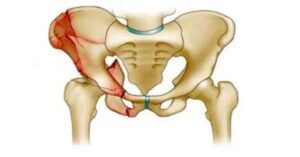

Kırığın tipi ameliyat kararında önemli bir rol oynar. Eğer kırık kemik parçalarının yer değiştirmesine neden olmuşsa cerrahi müdahale gerekebilir. Aynı şekilde eklem yapısını etkileyen kırıklarda da ameliyat tercih edilebilir. Çünkü bu tür kırıkların doğru şekilde iyileşmesi için kemiğin sabitlenmesi gerekir. Bu sabitleme işlemi genellikle vida, plak veya protez gibi yöntemlerle yapılır.

Cerrahi işlem sırasında kırık kemik parçaları uygun pozisyona getirilir ve sabitlenir. Bu sabitleme işlemi vidalar veya plaklar kullanılarak yapılabilir. Bazı durumlarda kalça protezi de tercih edilebilir. Uygulanan yöntem kırığın yerine ve yapısına göre değişebilir. Bazı hastalarda kalça kırığı ameliyatı uygulanabilir. Bu işlem sayesinde kemik parçaları stabil hale getirilebilir. Bu sayede iyileşme sürecinin daha sağlıklı ilerlemesi hedeflenir.